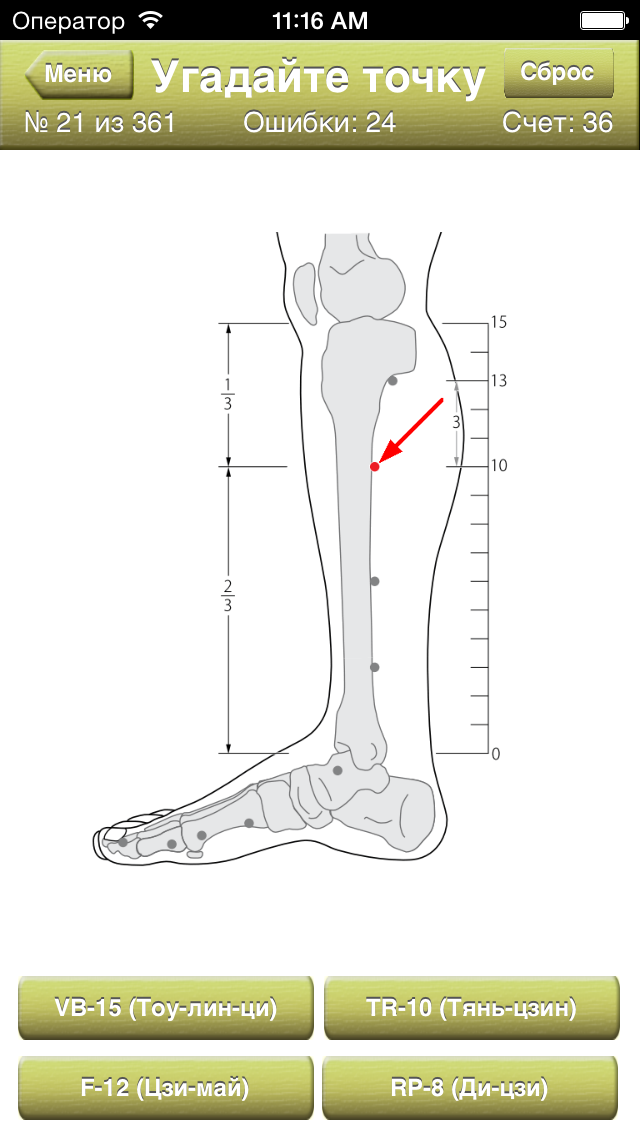

Скриншоты